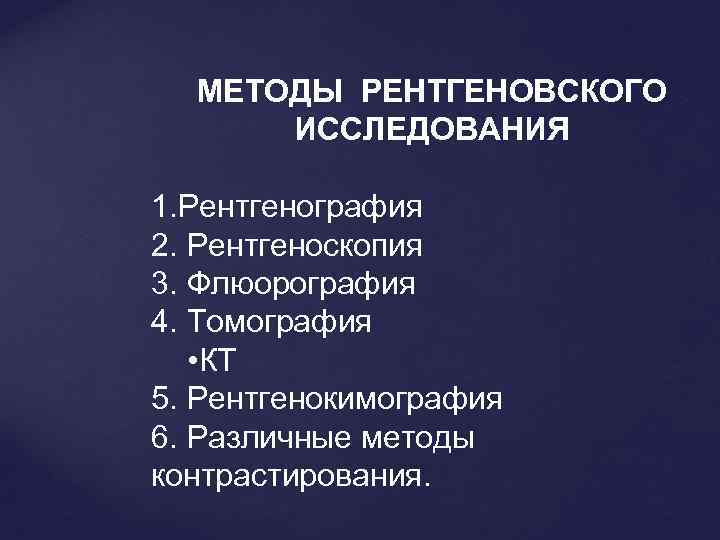

МЕТОДЫ РЕНТГЕНОВСКОГО ИССЛЕДОВАНИЯ 1. Рентгенография 2. Рентгеноскопия 3. Флюорография 4. Томография • КТ 5. Рентгенокимография 6. Различные методы контрастирования.

МЕТОДЫ РЕНТГЕНОВСКОГО ИССЛЕДОВАНИЯ 1. Рентгенография 2. Рентгеноскопия 3. Флюорография 4. Томография • КТ 5. Рентгенокимография 6. Различные методы контрастирования.